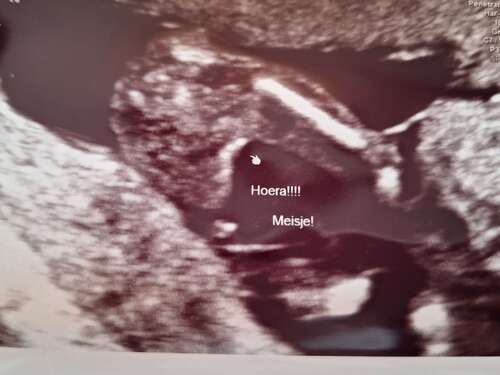

Met 15+2 een geslachtsbepaling echo laten doen en als verassing gelaten tot thuis, het is een meisje 🩷 Bij de 20 weken zelf kunnen kijken en zag toen erg duidelijk dat het geen jongetje is. Bij de laatste echo met 33 weken nog even dubbel check en is nog steeds een meisje! Ik moet nog zo'n 6 weken dus 100% weet ik het nog steeds niet 😜